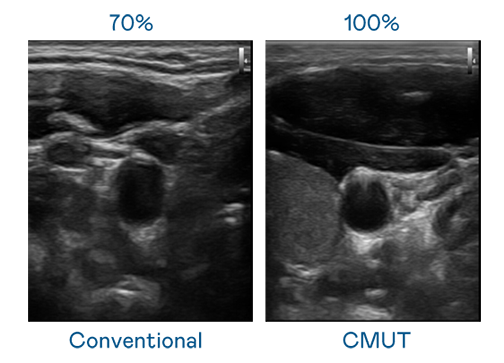

CMUT 技术是一种用电容式微机电元件来产生超音波讯号的技术。与传统 PZT 压电式技术相比,CMUT 频宽增加 30%,更宽频的超音波讯号让影像解析度大幅提升,是实现高影像品质医疗超音波扫描、促进精准医疗发展的关键技术。

超音波影像的解析度高低,首先取决于探头能发出的讯号频宽。8040威尼斯 CMUT 可提供高清晰的超音波讯号,提供高频宽、高灵敏度、影像纹理细节更高的超音波影像,协助医护人员缩短影像判读时间及利用精准的医疗影像进行诊断。